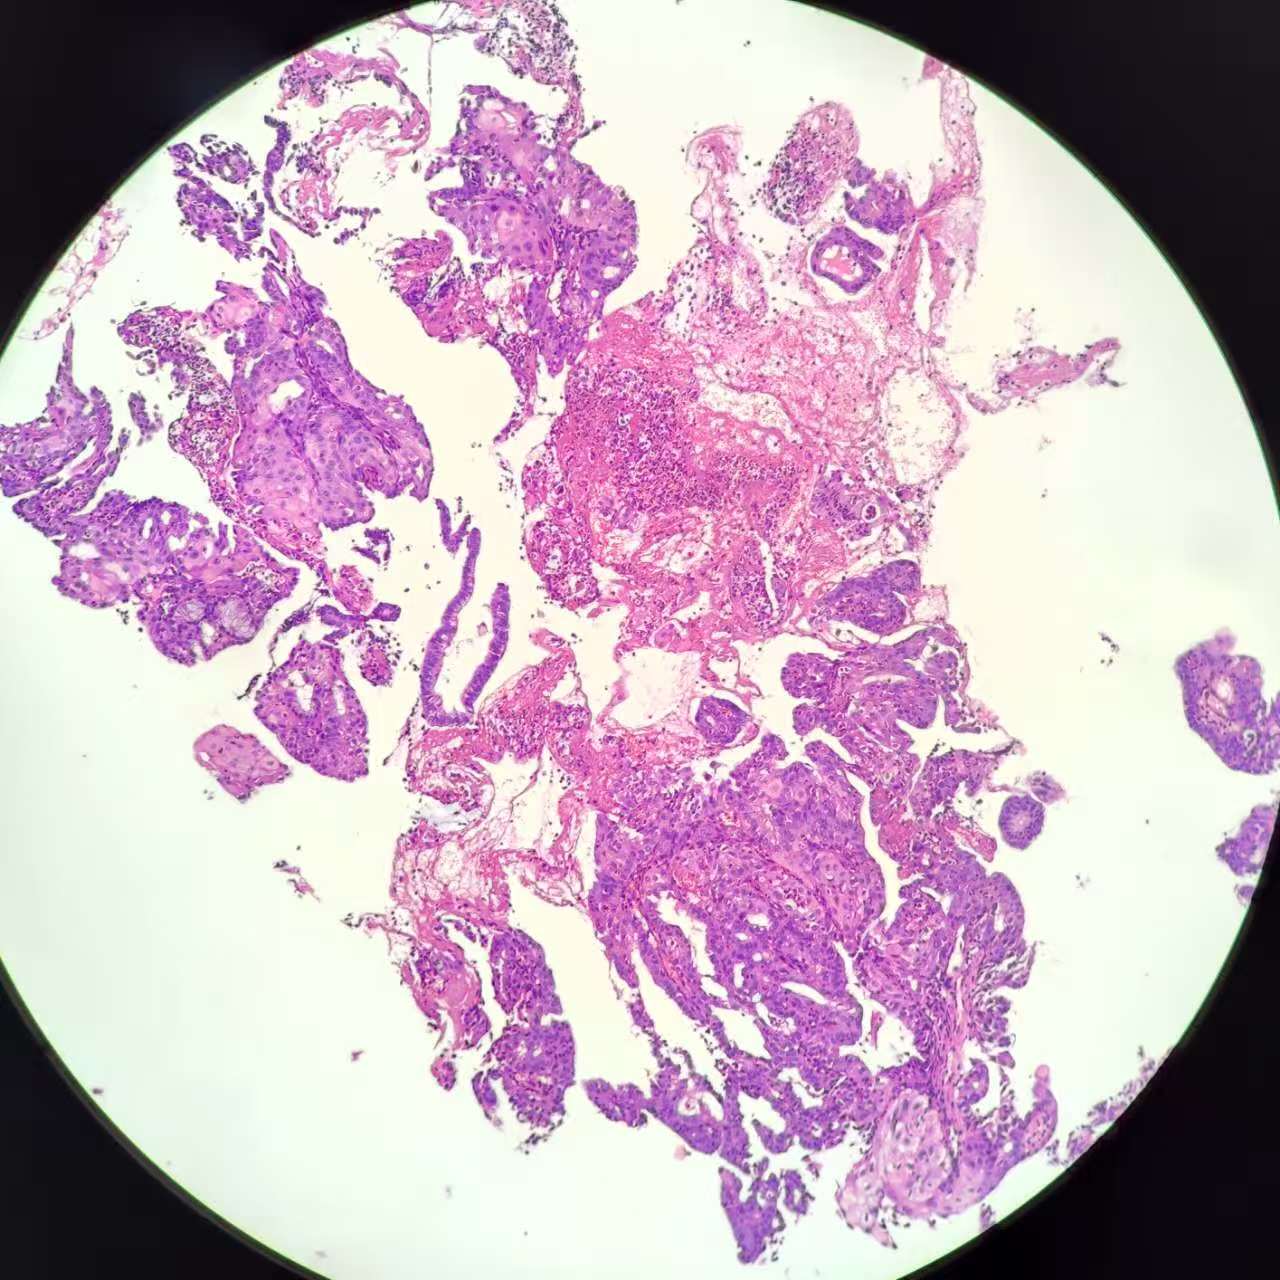

性别

女

年龄

51岁

临床诊断

子宫 内膜息肉?

一般病史

绝经三年,近期阴道出血,宫腔镜见后壁槽杂样组织,质脆

标本名称

子宫内膜诊刮

大体所见

灰红碎组织1堆

复杂性增生?部分区域腺体融合似成实性,癌?局部内膜腺体鳞化还是宫颈鳞上皮病变(第1张图和最后一张)?

考虑子宫内膜样腺癌,伴有鳞状分化。